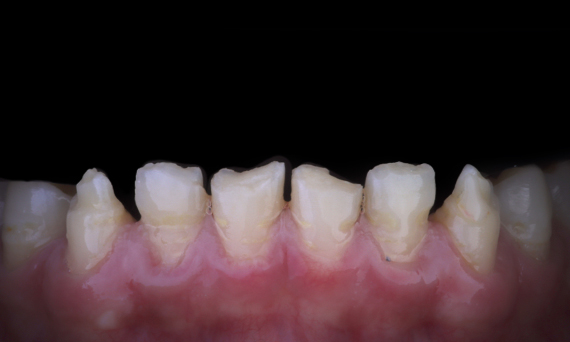

Amelogenesis Imperfecta

Full mouth rehabilitation with 28 all-ceramic restorations

A particular and protracted case of skeletal Class II malocclusion and generalized amelogenesis imperfecta in a teenager was referred for prosthetic rehabilitation. The aim of the treatment was to prepare the remaining tooth structure, remove undercuts, and make room for all-ceramic crowns covering the entire dentine and simulating the lost enamel.

Before: Initial situation prior to orthodontic treatment.

After: Final result, 1 week post-operative.